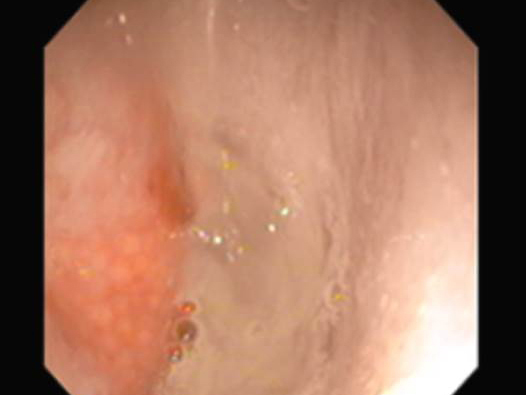

呼吸様式がおかしく鼻がつまった様な呼吸になったマルチーズの鼻腔内観察および生検を行ないました。

今回は麻酔下にて口から5.5mmの内視鏡を、鼻から2.8mmの内視鏡をいれ、咽頭部および鼻腔内の観察の両方を行いました。

左が咽頭部の写真です。粘膜面も綺麗で異常はありません。

右が鼻腔内の写真です。写真の左側に発赤、右側には粘液性の過剰分泌物が確認されました。

現在、適切な治療により状態は安定しております。